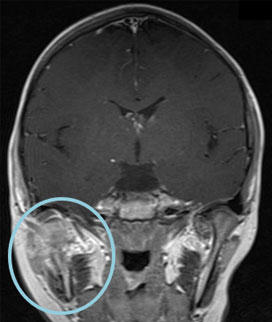

右下顎骨にLCHの骨再発をきたした。HU内服治療を開始後、溶骨部分の順調な修復が認められた。

MRI T1造影

ハイドロキシウレア開始時